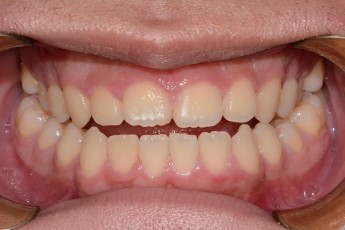

BEFORE & AFTER

- 돌출입교정